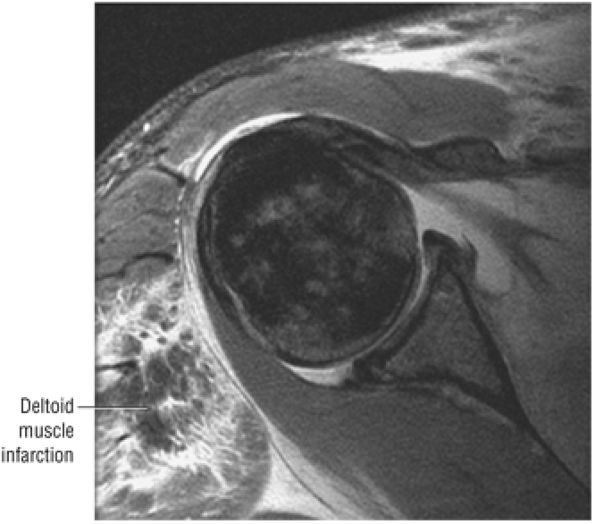

routine shoulder MR examination, when edema and hemorrhage are seen adjacent to the biceps tendon along the proximal humeral shaft. The large arc of muscle bundles making up the deltoid muscle are visualized on axial images anterior, lateral, and posterior to the humeral head and rotator cuff muscles.